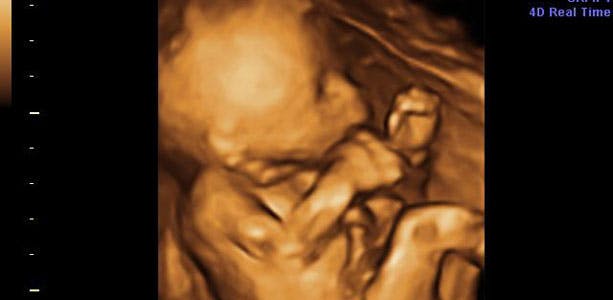

Gravid uge 19: Hørelsen udvikles

Mellem uge 15 og 20 udvikles hørelsen, og selvom barnet ligger godt beskyttet inde i livmoderen, hører det konstant lyde fra dit hjerte, der slår, tarmene der arbejder og bobler, samt når du nyser, hoster eller ler. Huden er dækket af fosterfedt og tjener det formål at beskytte huden mod fostervandet. I slutningen af ugen måler barnet cirka 19 centimeter og vejer omkring 380 gram. Hovedet måler cirka 4,5 centimeter i diameter.